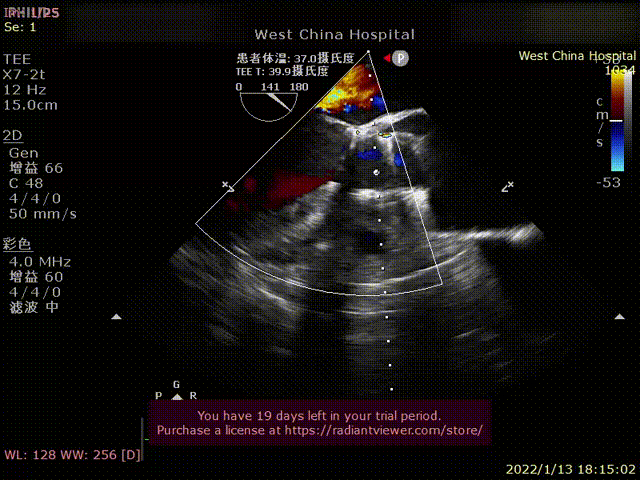

患者为68岁男性,因“胸闷、气促4余年,加重一年”主诉入院。术前超声心动图提示:左心增大,左室为著,左室壁肥厚,LVDD90 mm,LVEF35%,主动脉瓣右冠瓣脱垂、重度反流。术后即刻主动脉瓣大量反流消失,LVDD缩小至84 mm,左室较术前明显缩小。

术前超声影像